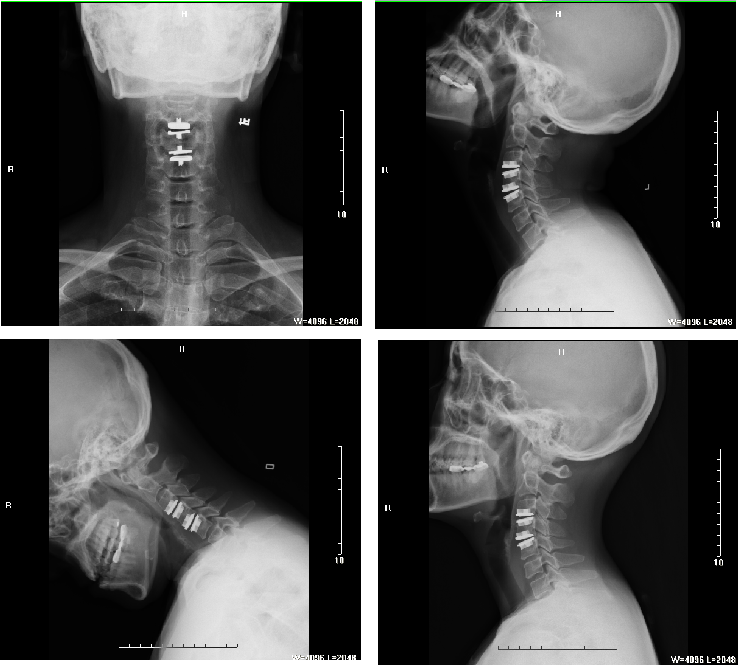

颈椎人工椎间盘置换术

通过切除病变颈椎间盘并植入人工颈椎间盘的方式,能够保证颈椎活动度及颈前凸,同时能够减少邻近椎体退变,降低相邻节段椎间盘疾病新发率,是颈前路植骨融合术的良好替代选择。